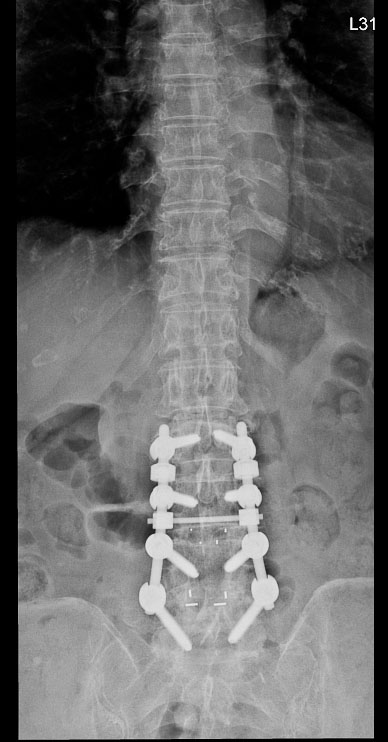

高齡翻修手術:

截釘技術降低風險

脊椎手術中最具挑戰性的情況之一,是需要再次手術的「翻修病例」。林英超主任說明,需要「翻修」的病人通常曾接受過脊椎固定手術,患部組織已形成疤痕與沾黏,再次手術時神經受傷風險提高。此外,翻修病人多屬高齡,往往伴隨骨質疏鬆或慢性疾病。

八十五歲的林女士在十多年前與七、八年前曾分別接受兩次腰椎手術,近來卻出現劇烈腰痛,翻身時疼痛指數高達八分,甚至難以入睡。影像檢查發現,她的腰椎第一與第二節出現嚴重狹窄,需要再次手術。

神經醫學中心團隊採用「截釘翻修技術」,處理高齡與多次手術史的複雜個案。「截釘翻修技術」的概念並非完全拆除舊有植入物,而是在原有固定系統仍可利用的情況下,截短或延伸固定桿,再重新連接新的固定結構,如此可以避免大範圍拆除植體與肌肉剝離。

林女士的手術過程順利,術後十天疼痛感即明顯緩解。兩個月後,她已能每天步行半小時,生活品質大幅改善。對她而言,最大的改變是終於能夠「一覺睡到天亮」。

神經醫學中心統計顯示,近兩年共有五十多名患者接受截釘翻修手術,平均出血量比傳統延長固定手術少約一百五十毫升。對於高齡或慢性病患者而言,出血量減少意味著感染與心血管負擔也隨之降低。

術前

術後

林女士術前與術後的影像檢查結果。